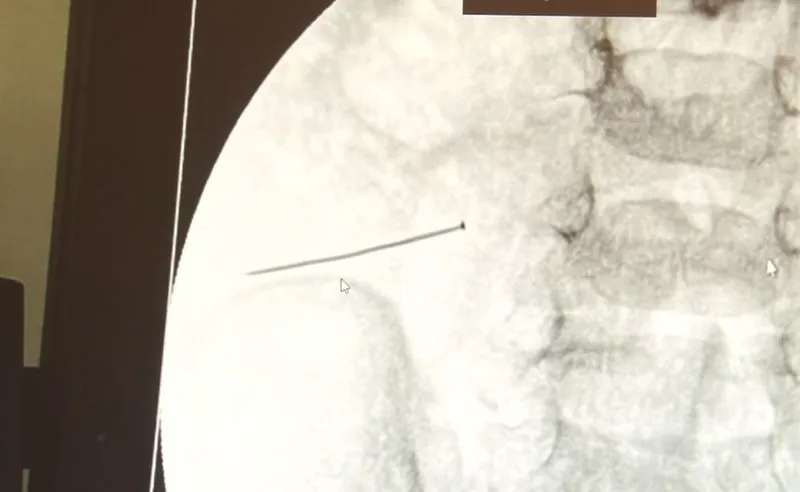

İstanbul’da 2 yaşındaki çocuk iddiaya göre 3 santimlik iğne yuttu, bağırsağı delen iğne başarılı operasyonla çıkarıldı. Ameliyatı gerçekleştiren Çocuk Cerrahisi Uzmanı Doç. Dr. Sefa Sağ, "Yaklaşık 3 santim boyunda bir toplu iğnenin ince bağırsağı deldiğini ve içeriğin de karın içerisine dolduğunu gördük. Ameliyatı başarılı bir şekilde tamamladık, yaklaşık 1 saat süren bir ameliyattı. Çok ciddi bir karın ağrısı, kusma söz konusuydu, ameliyatını yapmasaydık Allah göstermesin çocuğun ölümüyle sonuçlanabilecek bir hadiseydi, çok dikkatli olunmalı" dedi.

İstanbul’da 2 yaşındaki çocuk iddiaya göre toplu iğne yuttu sonrasında adeta karın ağrısıyla yerinde duramaz hale geldi. Babaanne, küçük çocuğun şikayetleri üzerine Şehit Prof. Dr. İlhan Varank Sancaktepe Eğitim ve Araştırma Hastanesi’ne götürdü. Burada yapılan tetkiklerde 2 yaşındaki çocuğun ince bağırsağında yaklaşık 3 santimlik toplu iğne olduğu ve bağırsağı deldiği belirlendi. Görüntülemeler sonrası 30 Ekim akşamı Çocuk Cerrahisi Kliniği Eğitim ve İdari Sorumlusu Doç. Dr. Sefa Sağ ve ekibi hemen ameliyata girdi. Başarılı operasyonla iğne olduğu noktadan alınırken aile de rahat bir nefes aldı. Doç. Dr. Sağ ise taburcu edilen hastasının durumuna ilişkin bilgi verirken yabancı cisim yutmalarına karşı ailelere önemli uyarılarda bulundu.

Çocuklarda yabancı cisim yutulmasına yönelik konuşan ve hastasına ilişkin bilgi veren Doç. Dr. Sefa Sağ, "Soluk borusuna kaçması durumunda çocuğun Allah göstermesin ölümüyle veya ömür boyunca yatağa bağımlı kalmasıyla neticelenebilecek sonuçlar doğurabiliyor. Yutulması durumunda da gastrointestinal sistemin herhangi bir yerine takılmadığı müddetçe ekseriyâ yabancı cisimlerin dışarıya çıkmasını bekliyoruz. Yabancı cisim yutulmasını 2 grupta inceleyebiliriz. Sıvı ve katı cisimler olarak sıvı; evde kullanılan kimyasal temizlik malzemelerinin yutulması çok ciddi problemler oluşturabilmekte. Ağızda, yemek borusunda ve midede yanıklar meydana getirebilmekte. Uzun dönemde çocukların hayat kalitesini oldukça etkileyen sonuçlar doğurabilmekte. Katı cisimlerden de ekseriyâ kendiliğinden çıkmasını bekleriz ancak böyle delici, kesici aletlerin yutulmasında ise herhangi bir bağırsağın veya gastrointestinal sistemin bir parçasında delinmeler meydana getirebiliyor. Bu çocuğumuzda da aynen böyle bir hadise meydana gelmişti. Sanırım 1 gün önce ailenin yuttuğunu tahmin ettiği bir yabancı cisim; toplu iğne. Ertesi gün bağırsakta delinmeyle sonuçlanmış ve çocukta da ciddi semptomlar meydana getirmişti. Bu şekilde hasta bize başvurdu. Tetkikler sonucunda yabancı cismi tespit ettik, semptomları ve bulgularına göre de çocuğu ameliyata aldık. Yaklaşık 3 santim boyunda bir toplu iğnenin ince bağırsağı deldiğini, ince bağırsaktaki içeriğin de karın içerisine dolduğunu gördük. Ameliyatı başarılı bir şekilde tamamladık, yaklaşık 1 saat süren bir ameliyattı" dedi.

Öte yandan, yaklaşık 3 santimlik toplu iğne filme yansıyan görüntüsüyle gözler önüne serildi.